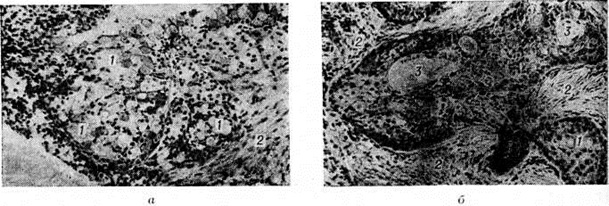

Течение заболевания обычно очень медленное, вначале не сопровождается никакими субъективными ощущениями или объективными признаками. От момента травмы или воспалительного процесса до появления первых признаков заболевания проходит 1—2 года, а иногда 15—20 лет. Характерные признаки Мукоцеле— появление эластической припухлости у медиального угла глазницы и постепенное смещение глазного яблока кнаружи и книзу, нередко слезотечение из соответствующего глаза. Поэтому больные Мукоцеле в первую очередь обращаются к окулисту. Припухлость покрыта нормальной кожей, в стадии истончения костных стенок при пальпации иногда определяется характерный пергаментный хруст. Вследствие увеличивающегося растяжения пазухи смещение глазного яблока усиливается, появляется ограничение его подвижности; зрение обычно не страдает. Диагностика возможна с момента деформации костных стенок придаточных пазух. Для уточнения диагноза необходимо рентгенологическое исследование в нескольких проекциях. Поражение лобной пазухи встречается чаще (до 75%), чем других придаточных пазух. Первым признаком кистовидного растяжения лобной пазухи является опускание её дна в глазницу, вследствие чего образуется характерное выпячивание в области верхнемедиального угла глазницы — глаз отклоняется кнаружи и книзу (рисунок 1). Дифференциальный диагноз проводят с мозговой грыжей (смотри полный свод знаний Головной мозг, грыжи). Раннюю стадию Мукоцеле можно смешать с опухолью или кистой слёзного мешка. При надавливании на кисту появляется гной из слёзной точки или киста уменьшается за счёт истечения гноя в полость носа. С целью дифференциальной диагностики проводят рентгенологическое исследование, при котором иногда определяются остеомы, остеосаркомы, карциномы и другие опухоли. Первым признаком Мукоцеле решетчатого лабиринта является выпячивание бумажной пластинки и слёзной косточки и отклонение глаза кнаружи (рисунок 2). Кистовидное растяжение клиновидной и верхнечелюстной пазух наблюдается редко. Лечение Мукоцеле придаточных пазух носа оперативное; рекомендуется наружное вскрытие соответствующей придаточной пазухи, так как при эндоназальном подходе при множественном кистозном растяжении можно оставить невскрытыми другие кисты. Прогноз во всех случаях Мукоцеле, не осложнённого вторичной инфекцией, можно считать благоприятным. Смотри полный свод знаний Придаточные пазухи носа. Причиной развития мукоцеле червеобразного отростка является, как правило, облитерация просвета червеобразного отростка на ограниченном участке вследствие перенесённого ранее воспалительного процесса. В образовавшейся замкнутой полости скапливается слизь. Диаметр кисты может быть от 0,5 до 10—12 сантиметров. Иногда полость заполнена белесоватыми шариками слизи. Такой патологический процесс называется миксоглобулёзом (смотри полный свод знаний). В результате растяжения стенки отростка все слои его атрофируются, замещаются соединительной тканью. Обычно Мукоцеле обнаруживают при операциях, предпринимаемых по поводу острого или хронический аппендицита, которые имеют сходную клинические, картину с Мукоцеле червеобразного отростка. Мукоцеле может вести к развитию кишечной непроходимости, возникновению аденокарциномы червеобразного отростка, псевдомиксоматозу брюшины. Лечение Мукоцеле червеобразного отростка оперативное и должно состоять в его удалении. Смотри полный свод знаний Аппендикс.